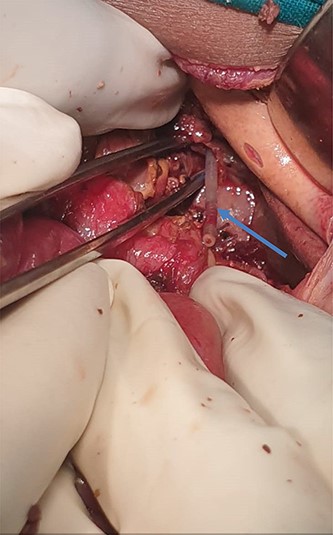

He was then prepared for exploratory laparotomy, and intraoperative gastrointestinal fluid of about 200 ml was noted and drained (Fig. 1).

Intestinal fluid leaking into peritoneal cavity, with change in color of the proximal jejunum.